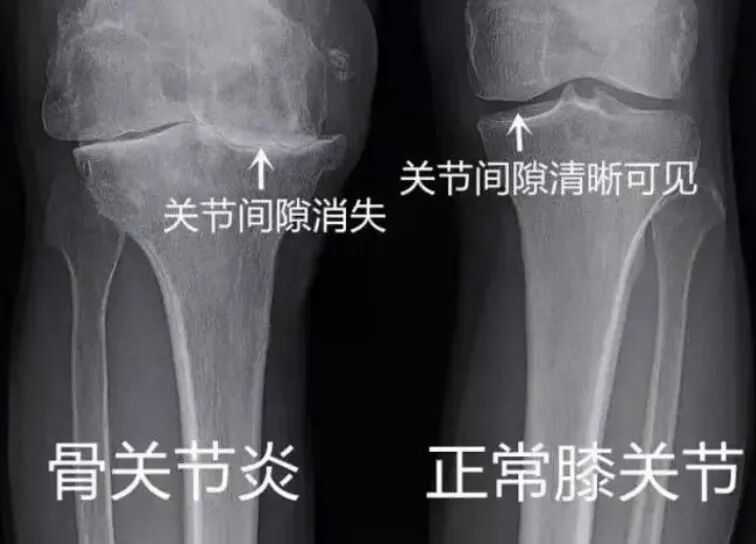

骨关节炎又称退行性关节炎,是一种以关节软骨损伤、破坏和继发性骨质增生为特征的慢性疾病。关节软骨就像关节间的“缓冲垫”,能减少骨骼摩擦、分散压力,而随着年龄增长、损伤累积等因素,这层“缓冲垫”会逐渐变薄、磨损,甚至出现破损,导致骨骼直接摩擦,引发疼痛、僵硬等症状。

骨科刘海亮主任讲到,它好发于膝关节、髋关节、脊柱及手指关节等负重部位,临床上表现为进展性关节疼痛,还可能伴随晨僵、关节肿大、骨擦音(活动时关节发出“咔咔”声)、关节无力等症状。值得注意的是,晨僵持续时间通常较短,一般几分钟到十几分钟,很少超过30分钟,这也是骨关节炎与类风湿关节炎的区别之一。膝关节骨关节炎的治疗目的是为了缓解疼痛及相关症状,减轻关节僵硬及肿胀,维持及改善关节功能,减少病残,提高生活质量。